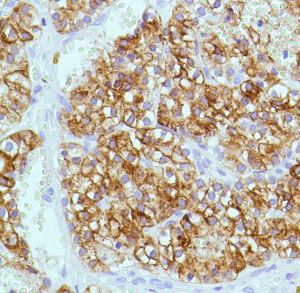

Parathyroid Hormone (PTH) (SP151)

Parathyroid hormone (PTH) is secreted by parathyroid cells. PTH increases blood Ca2+ levels by dissolving the salts in bone and preventing their renal excretion. Most PTH is secreted in its intact, mature 9.5 kDa form, amino acids 1-84; however, it can also be secreted as N-terminal truncated fragments or C-terminal fragments after intracellular degradation, as in the case of hypercalcemia.